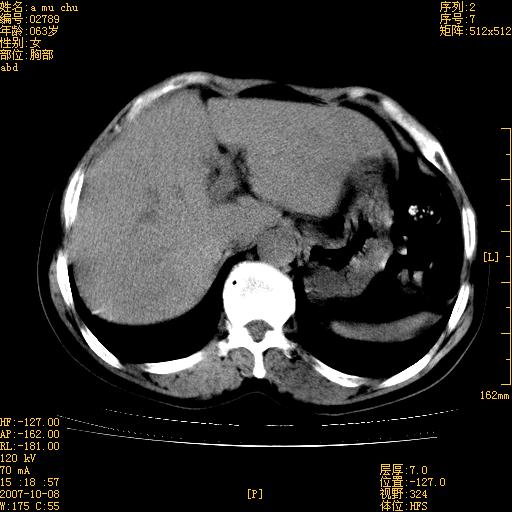

以下是引用王维浦在2007-10-17 21:02:00的发言:[br]胆囊增大,囊壁明显不规则增厚,邻近肝组织浸润,肝内外胆管无扩张。诊断:胆囊ca;[br]胰头软组织肿块影,考虑是由转移肿大的胰后淋巴结、没有肠道准备的十二指肠及胰头共同形成。[br]

以下是引用zhangzexing在2007-10-18 7:13:00的发言:[br]支持胰头占位,慢性胆囊炎. 2.肝左叶前外侧段占位,血管瘤?建议增强

以下是引用影像实习生在2007-10-17 19:49:00的发言:[br]支持胰头占位,慢性胆囊炎. 2.肝左叶前外侧段占位,血管瘤?建议增强.

以下是引用刘振江在2007-10-17 19:42:00的发言:[br]没有增强,胰头癌?胆囊及肝左叶占位?